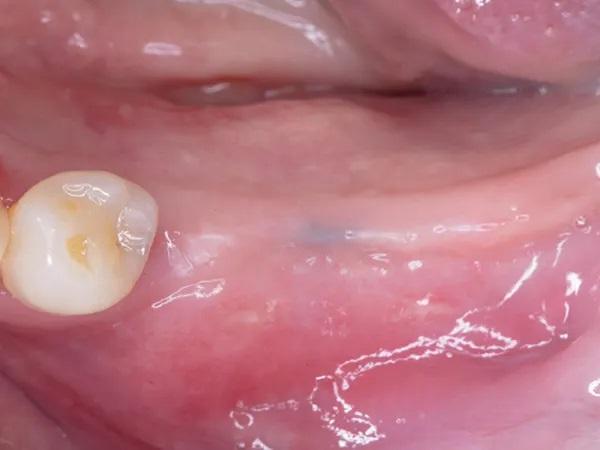

Женщина, 63 года, с неотягощенным анамнезом, явилась для восстановления левого квадранта нижней челюсти; в нем отсутствовали левые первый и второй моляр, а также были поражены второй премоляр и третий моляр, причем последний был наклонен мезиально из-за преждевременной потери второго моляра (Фото 2 и Фото 3). Было запланировано удаление разрушенных зубов с одновременным восстановлением гребня на участке дефекта от второго моляра до первого премоляра с помощью костного трансплантата и рассасывающейся коллагеновой мембраны.

Фото 2: (Случай 1) Вид c окклюзионной стороны перед операцией; обратите внимание на отсутствие первого и второго моляров нижней челюсти слева и связанную с этим потерю объема тканей.